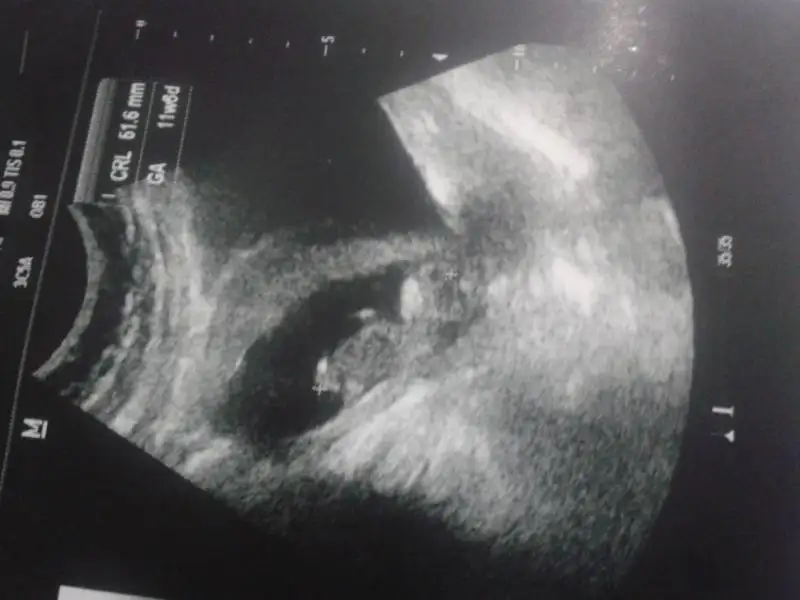

Eki Görüntüle 923209 Eki Görüntüle 923209 Eki Görüntüle 923210

(( ya aslında şimdi belli olmuştur benimki ama kesin olsun diye haftaya gideceğim doktora

Kacnci haftadasin canm

16. haftadayım. haftaya 17 olacağım o zaman kesin olur hem